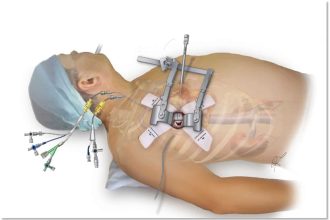

مقارنة بين عملية القلب المفتوح و جراحة القلب بالمنظار